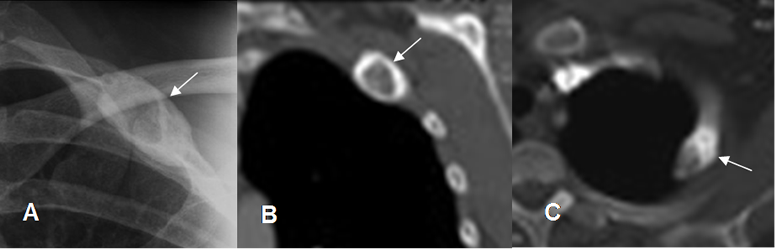

Fig 40. Displasia fibrosa.

A: Rx AP, B: TAC reconstrucción coronal y C: TAC axial. Lesión expansiva de bordes escleróticos en la 2º costilla, por displasia fibrosa.